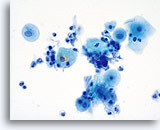

Postpartum

High power view of parabasal cells during postpartum. Note presence of glycogen and low N/C ratio. 60X